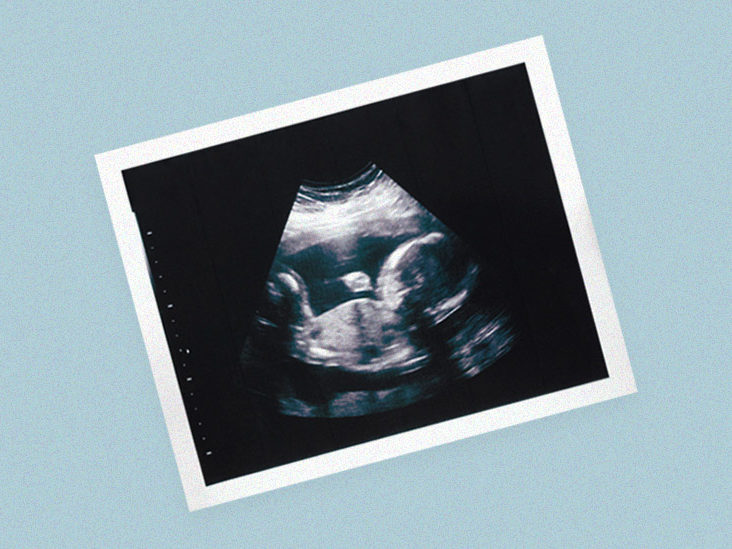

Ultrazvočni pregledi v nosečnosti